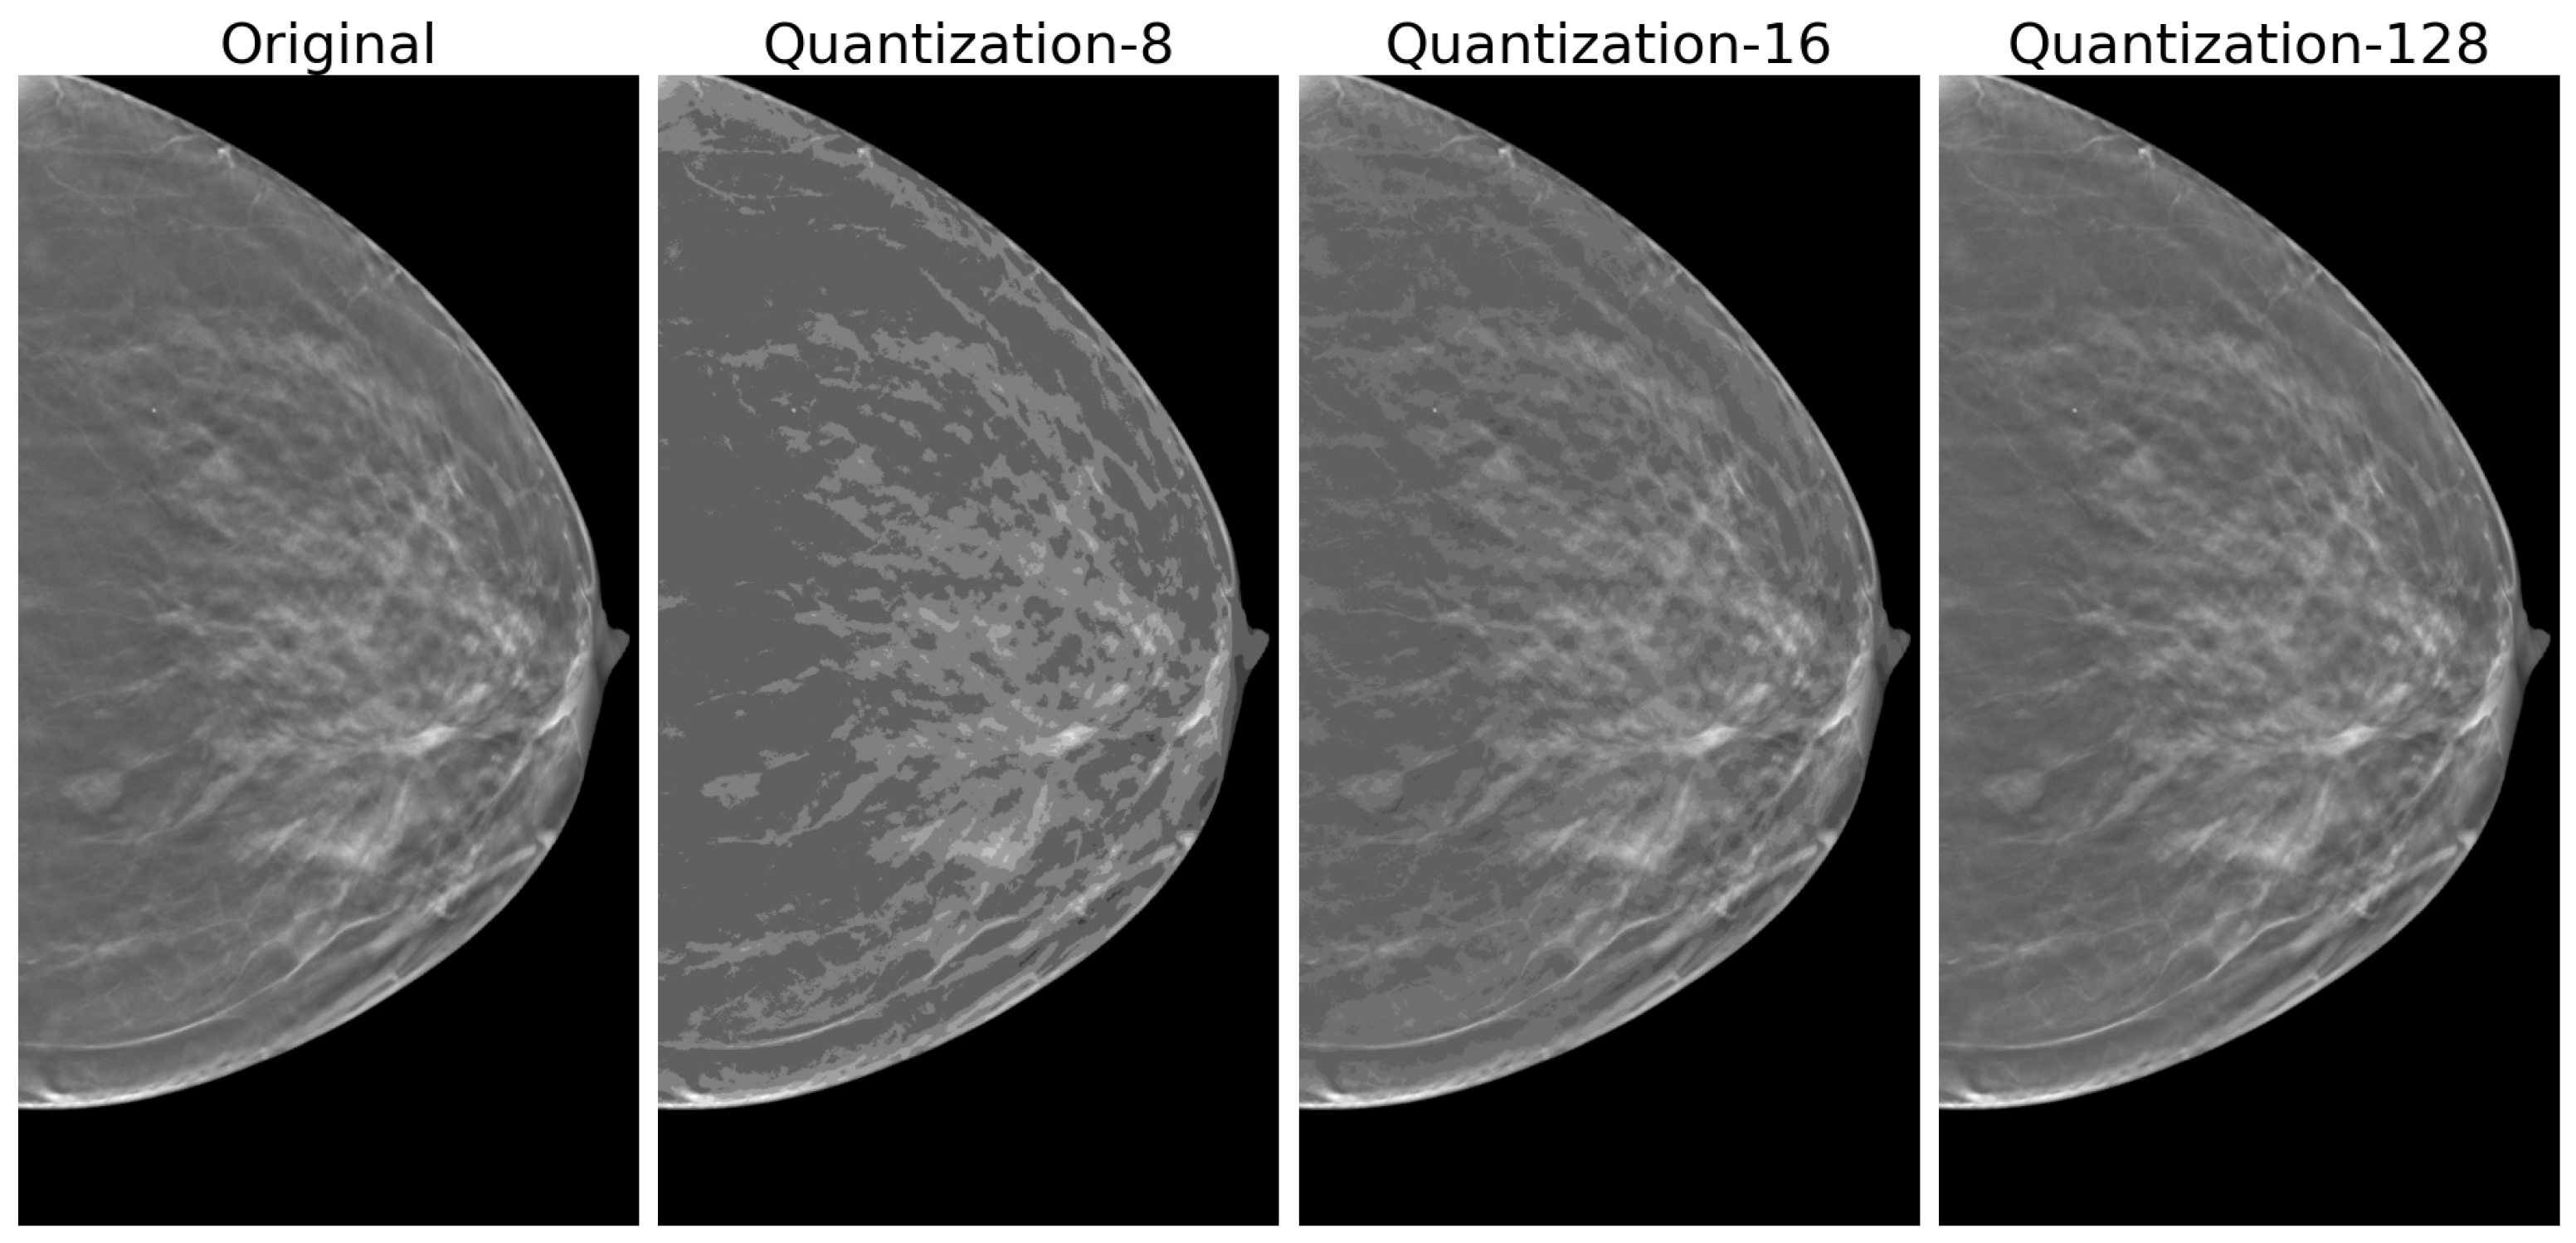

2.4.1. Quantization

3.2. Quantization Effects